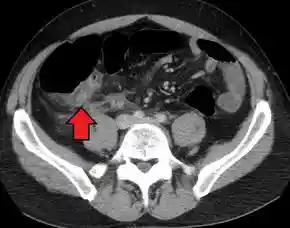

![]()

Appendicitis as seen on CT imaging

A fecalith marked by the arrow that has resulted in acute appendicitis.

Where it is readily available, computed tomography (CT) has become frequently used, especially in people whose diagnosis is not obvious on history and physical examination. Although some concerns about interpretation are identified, a 2019 Cochrane review found that sensitivity and specificity of CT for the diagnosis of acute appendicitis in adults was high.[49] Concerns about radiation tend to limit use of CT in pregnant women and children, especially with the increasingly widespread usage of MRI.[50][51]

The accurate diagnosis of appendicitis is multi-tiered, with the size of the appendix having the strongest positive predictive value, while indirect features can either increase or decrease sensitivity and specificity. A size of over 6 mm is both 95% sensitive and specific for appendicitis.[52]

However, because the appendix can be filled with fecal material, causing intraluminal distention, this criterion has shown limited utility in more recent meta-analyses.[53] This is as opposed to ultrasound, in which the wall of the appendix can be more easily distinguished from intraluminal feces. In such scenarios, ancillary features such as increased wall enhancement as compared to adjacent bowel and inflammation of the surrounding fat, or fat stranding, can be supportive of the diagnosis. However, their absence does not preclude it. In severe cases with perforation, an adjacent phlegmon or abscess can be seen. Dense fluid layering in the pelvis can also result, related to either pus or enteric spillage. When patients are thin or younger, the relative absence of fat can make the appendix and surrounding fat stranding difficult to see.[53]